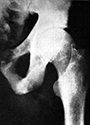

In 1947, J. Russell Davey, M.D., above, discovered fluorine poisoning showing generalized osteosclerosis in the X-ray of a Pennsalt worker in Easton, PA. The medico-legal position of the Atomic Energy Commission was that chronic fluorine intoxication rarely occurs in the United States. |

In a 31 January 1947 x-ray report, Lieutenant Davey, USNR inadvertently exposed Robert Kehoe's secret study monitoring workers exposed to HF at the Pennsylvania Salt Company on Hellertown Road in Easton, PA. X-ray film provides visual evidence of poisoning and its effect on the osseous system. "All of the films show osteosclerosis previously described and considered to be as a result of fluoride poisoning…Very truly yours, J. Russell Davey, M.D." My father was not aware of Kehoe's mission, to clandestinely collect medical data regarding poisoned workers in order to protect the U.S. government's bomb-related defense industry from potential lawsuits. Outraged AEC contractors identified Dr. Davey as "the offending radiologist." Not given the proper protocol, x-ray results were sent directly to the Pennsalt plant in Easton rather than Kehoe's Kettering Laboratory in Cincinnati, Ohio. Interpretations were routinely adjusted at Kettering to meet the needs of the AEC and Kehoe's corporate sponsors. Five days after the incident, at the age of 29, Dr. Davey wisely took out a large life insurance policy.